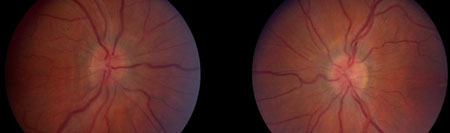

Os sinais que podem ser encontrados no exame físico incluem inchaço no disco óptico, paresia do sexto nervo e distúrbios da função sensitiva visual. A perda de campo visual é comum e o padrão prototípico da perda precoce é o aumento do ponto cego e perda inferonasal.[35] Os critérios modificados de Dandy podem ser utilizados como critérios de diagnóstico.[36][37][Figure caption and citation for the preceding image starts]: Edema bilateral do discoDo acervo pessoal do Dr. M. Wall; usado com permissão [Citation ends].

[Figure caption and citation for the preceding image starts]: Inchaço estabelecido bilateral do discoDo acervo pessoal do Dr. M. Wall; usado com permissão [Citation ends].